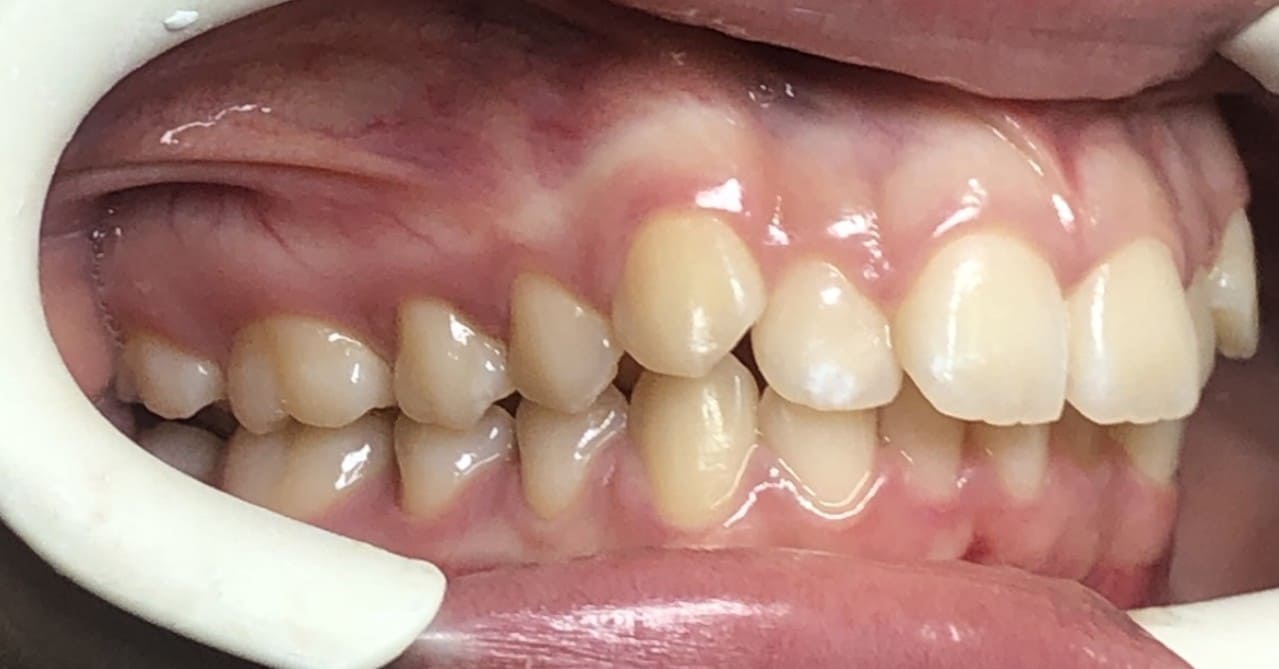

Initial

Final